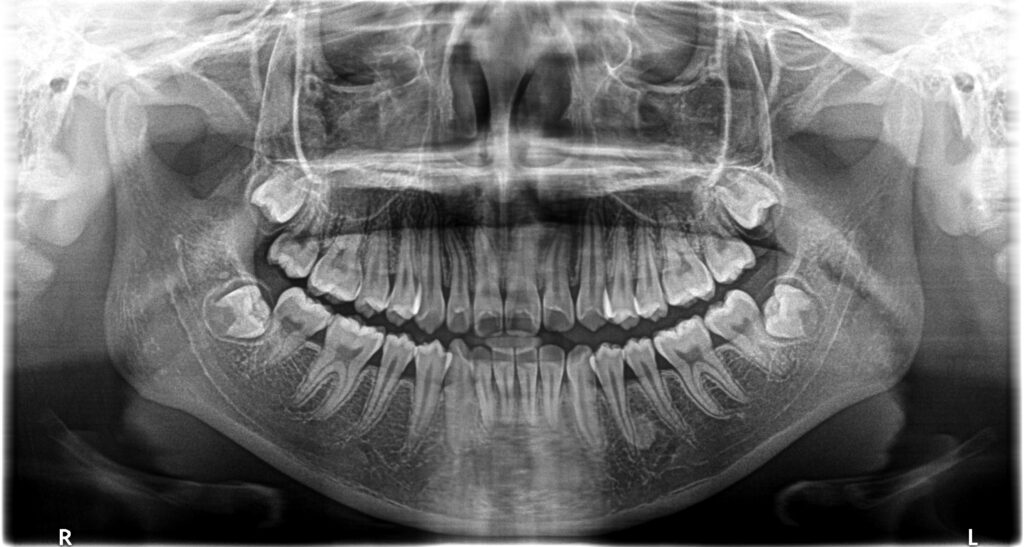

- 診断:2級過蓋咬合、上下永久歯(犬歯)萌出スペース不足

- 治療方針:非抜歯で行う。虫歯予防(フッ素)、歯磨き指導、上下拡大床→咬合関係改善のツインブロック(2級→1級関係へ)→マウスピース矯正→下親知らずの抜歯、保定→メンテナンス

13歳頃、永久歯列になったところで、1期治療終了。虫歯のコントロール、歯磨き指導も十分に行ったため、虫歯や歯肉炎の発生もなく理想的な状態で完了できたと思います。あとは、高校1~2年生くらいに下顎の埋伏親知らずを抜歯して、通えれば20歳くらいまで半年メンテナンスが良いかもしれません。本当に口腔内の良好維持を考えている歯科医は、矯正で一時的に治った状態に満足しません。後戻りも考慮して、適齢期の親知らずの抜歯を行ったり、習癖の改善に取り組むでしょう。さらに患者さんが通院可能であれば、予後も追い続ける傾向があるでしょう。

下顎前歯叢生予防のため、高校1年になり、左右下埋伏の親知らずの抜歯を行いました。本人歯並びが良くなって、ホワイトニングも希望されましたので、行うことになりました。かなり白くなりました。個人的にこれが本当の人工物に頼らない理想的な治療方法(矯正+ホワイトニング)だと思ってます。これをもって、私の治療責任は果たされ、治療終了となります。恐らくこの子は、今のままの予防概念であれば、今後歯のトラブルに遭遇する確率は低いと考えられます。